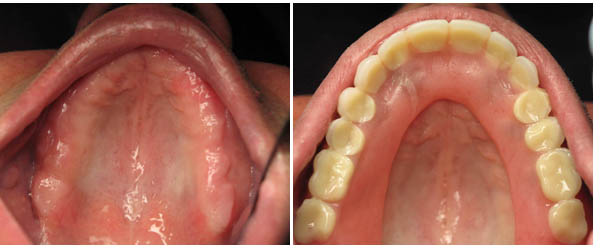

Mini Implant-Supported Denture/Existing Denture Conversion

Mini Implant-Supported Denture

Dentures